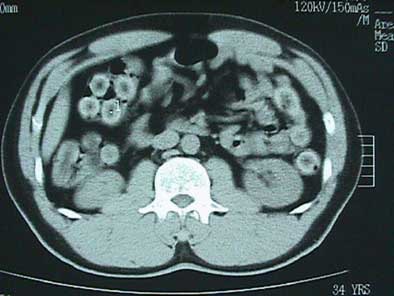

X-ray detected capsules in 59/70 patients (85%) and in all 70 patients (100%) imaged with CT. In these modalities the foreign bodies were seen as oval or rectangular densities surrounded by halos, said to represent air trapped within the Scotch tape or between two layers of condom. And for reasons the researchers do not yet understand, on CT the rims of the capsules were distinctively denser at 40 to 90 HU, while the centers were lucent at - 20 to -50 HU, Hussain said.

| Drug-bearing capsules with lucent halos can be seen in plain film image (above). In abdominal CT scout image (below), the lucent centers of the capsules contrast with denser rims. |